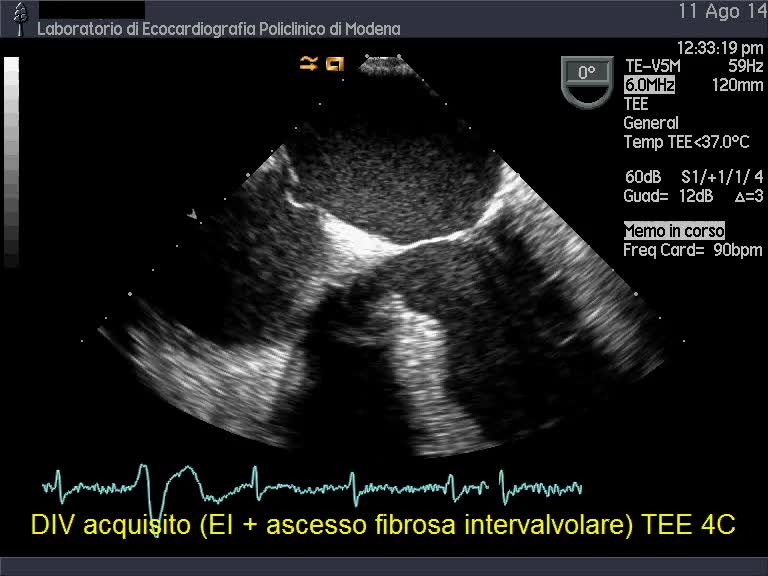

Titolo:

Ascesso della porzione mitroaortica e conseguente div perimembranoso

Autore:

Andrea Barbieri